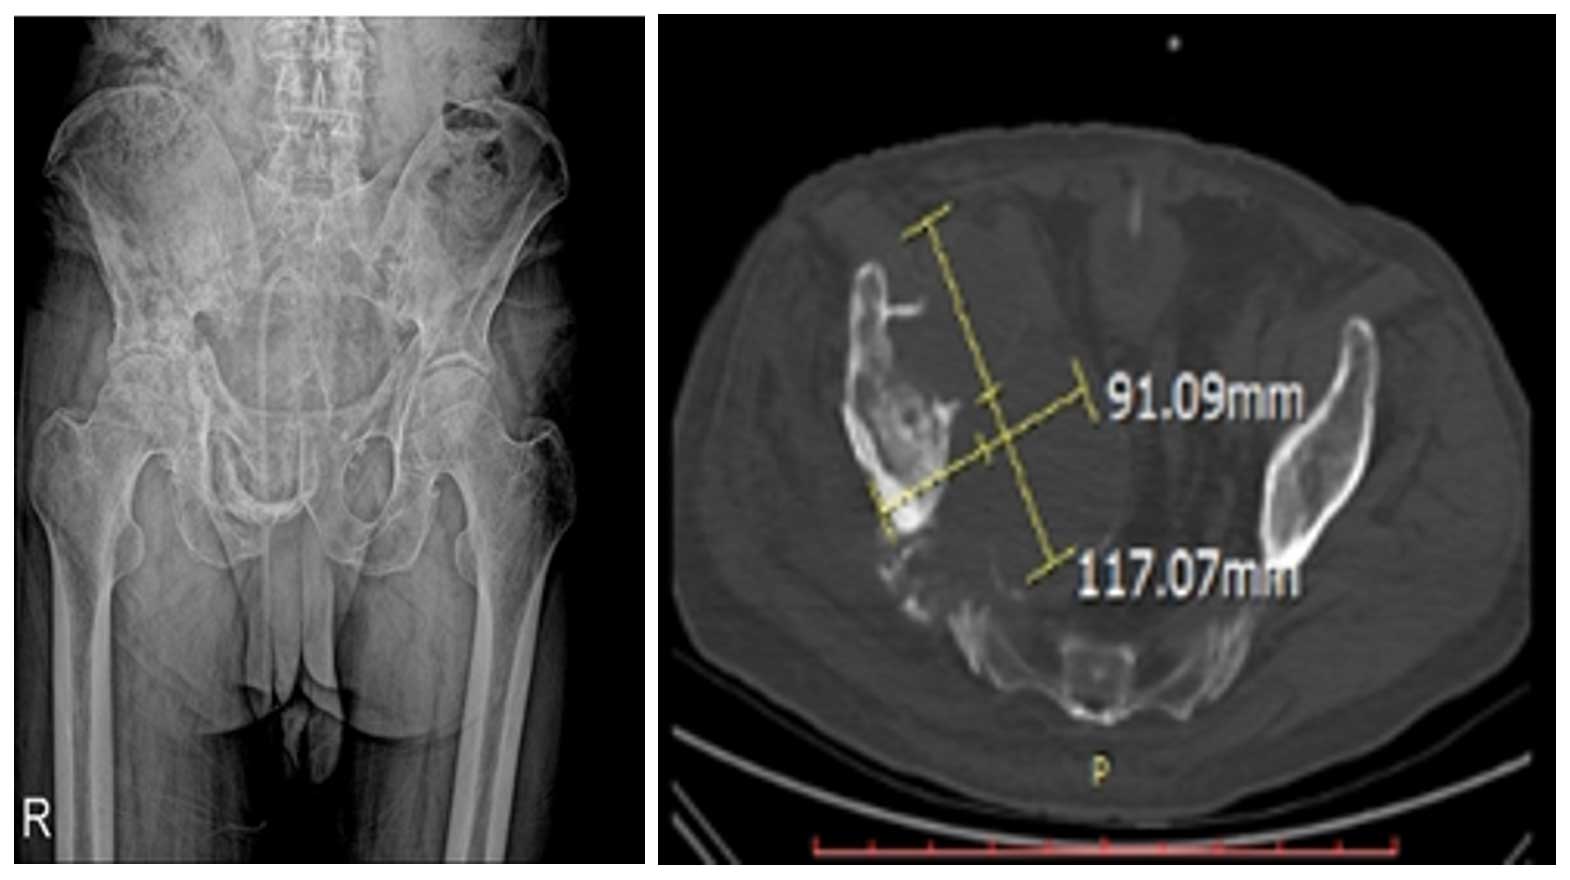

84 yaş erkek hasta, 7 aydır mevcut sağ kasık ve kalça ağrısı ile başvurmuş, yürümekte güçlük çekmektedir. İğne biyopsisinde kondrosarkom tanısı doğrulanmış ve taramalarda metastaz saptanmamıştır.

Ameliyat Öncesi: MR’da kemik harabiyetine eşlik eden büyük tümör dokusu görülmekte.